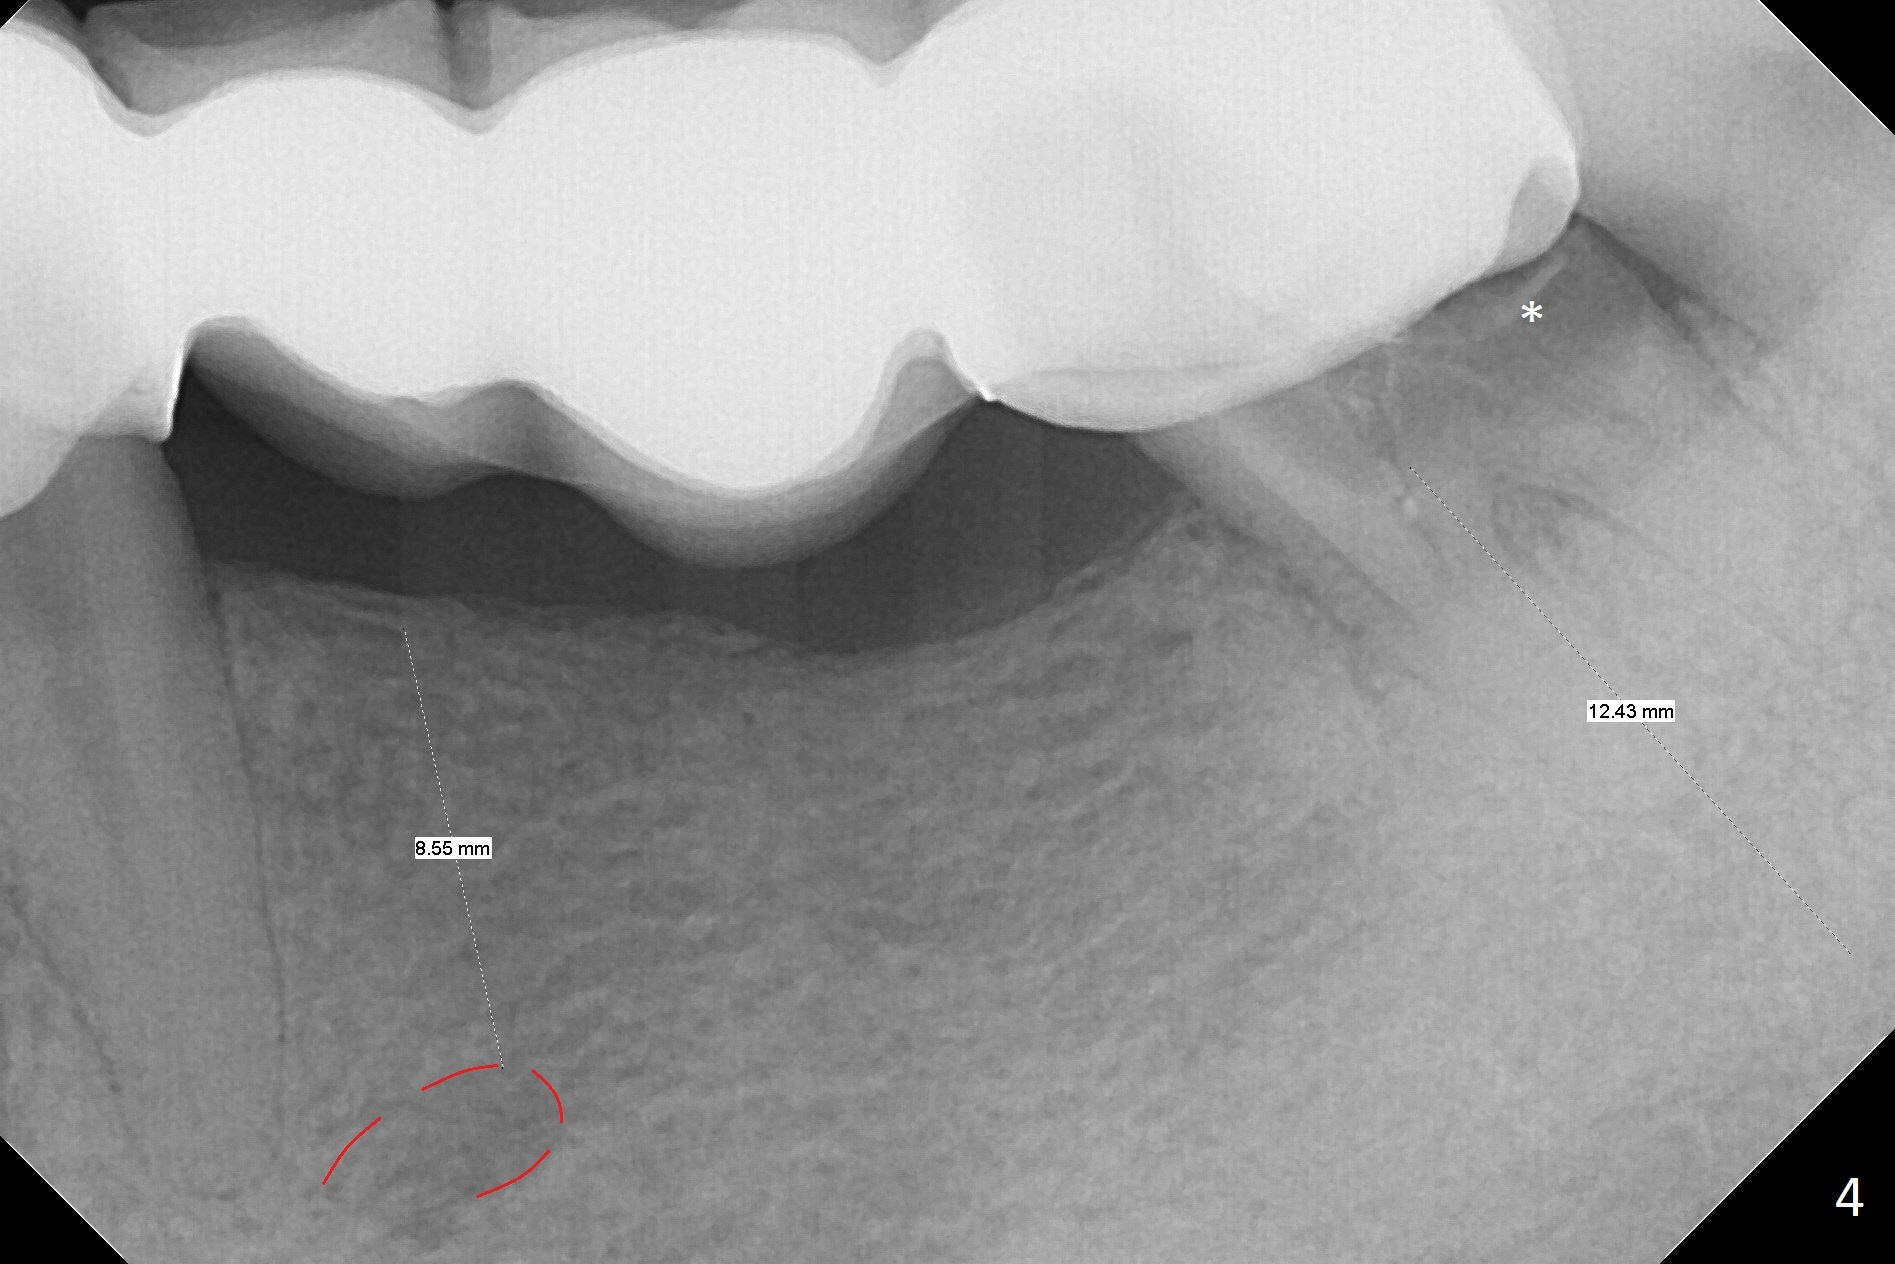

A 39-year-old woman has mobile FPDs at #2-6 (Fig.1,2) and 18-21 (Fig.3,4). Panoramic X-ray (Fig.1,3) was taken 10 years ago, while PAs (Fig.2,4) were taken lately. The abutment at #6 appears to be fractured (Fig.2 >), while that at #18 has 2nd caries (Fig.4 *). Removal of the FPDs determines salvageability of the abutments. The one at #6 may need RCT, B-U and crown or extraction/implant. In any event, implants will be placed at #3, 4, 18 and 20. To avoid the Inferior Alveolar Canal and Mental Loop, the implants will be as lingual as possible (Fig.3,4). For surgical and restorative stents, take Alginate impression as soon as the patient arrives.